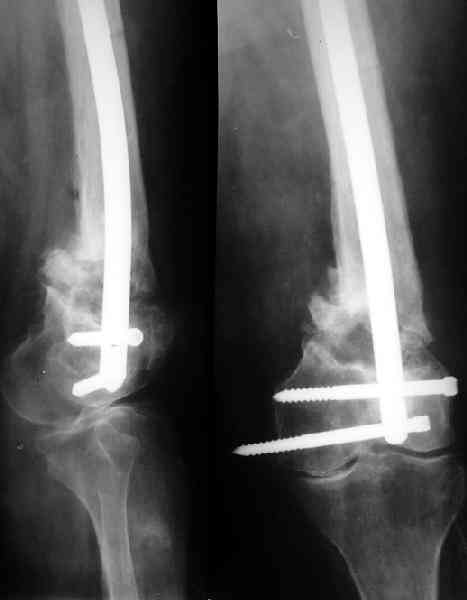

Аппарат для восстановления оси и длины тут действительно вполне уместен. И голень целесообазно врменно зафиксировать. А заштифтовать

можно и без голени, оставляя шансы на ту или другую мобилизацию коленного сустава.

Пример подобного ложного сустава в приложении.

На сегодня есть имплантаты с куда более продвинутой дистальной фиксацией.